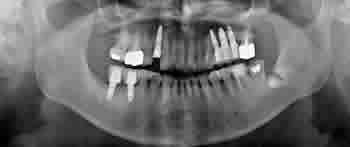

親知らず症例 ⑧

| 治療前 | 治療後 |

| 治療前 | 治療後 |